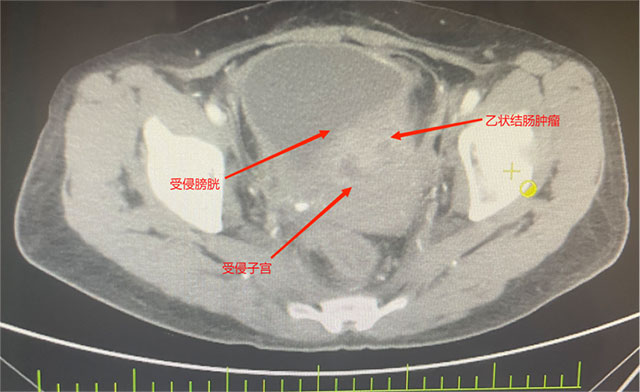

她被确诊为乙状结肠癌,肿瘤已“疯狂”侵犯膀胱、子宫、输尿管等多个盆腔脏器,还伴随不全性肠梗阻。2个月前在外院住院治疗,因手术风险大,外院仅为她做了横结肠造口术缓解梗阻,可术后不幸出现结肠膀胱瘘——小便中混着大便的症状让她痛苦不堪,叠加尿路感染、肿瘤引发的消化道出血,以及尿路梗阻导致的肾功能不全,多重并发症叠加,生活质量跌至谷底。

先是完整切除受肿瘤侵犯的直肠与乙状结肠原发灶,紧接着剥离与肿瘤紧密粘连的子宫及双侧附件并完整移除,随后小心翼翼分离膀胱与周围组织,将受侵膀胱全部切除——前三项切除手术已耗极大精力,团队仍需在腹腔镜下用回肠精心构建新的膀胱通路,确保患者术后排尿功能正常。